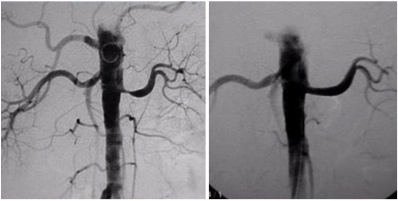

Estenose da artéria renal

Nos casos em que o tratamento se faz necessário, as estenoses (estreitamentos) das artérias renais é feito por técnicas endovasculare, ou seja, por dentro dos vasos sanguíneos.